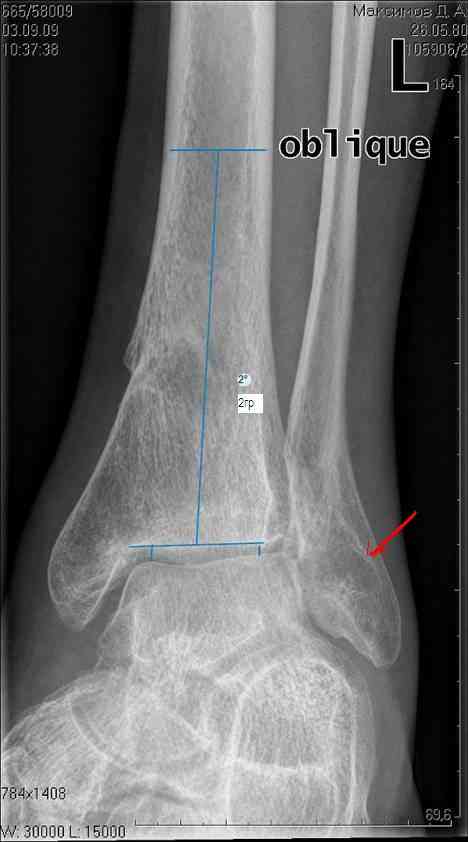

Здравствуйте коллеги. Представляю молодого человека 28 лет, получившего травму в апреле 2008года. Травму он получил на работе, левая голень со стопой оказались зажатыми между двумя тяжелыми предметами. В результате открытые переломы 1,2,3 плюсневых костей с размозжением мягких тканей над ними, открытый перелом наружной лодыжки со смещением дистального отломка кзади и подвывихом стопы кнаружи с размозжением мягких тканей над лодыжкой, закрытые переломы внутренней лодыжки и дистального метэпифиза большеберцовой кости.Учитывая наличие размозжения тканей стопы и области голеностопного сустава лечили в аппарате внешней фиксации. Переломы срослись, однако имеет место незначительный подвывих стопы кнаруже и неправильно сросшийся отломок наржной лодыжки (смещен кзади)Сегодня пациента ничего не беспокоит (с его слов. Клинически левый голеностопный сустав не отечный,пальпация всех структур данного сустава безболезненна. Имеет место ограничение тыльного сгибания стопы (сгибание к тылу стопы составляет до 10-15 гр), в связи с этим имеет место гиперподвижность в суставе Шопара. Пациент ходит со стельками (индивидуальные).Нужна ли пациенту реконструктивная операция в голеностопном суставе: исправление взаимоотношений в наружных отделах голеностопного сустава или что еще?С уважением Батал Шушания.

Наверное наружная лодыжка ушла назад не одна - такое впечатление, что был сломан и задний отдел б/берцовой кости (малоберцовая вроде прямая, а эпифиз широковат, как-то). Поэтому, думается, что гоняться за лодыжкой и синдесмозом не стоит. А вот вальгусный голеностоп и деф. артроз таранно-ладьевидного сустава - налицо. Вальгус надо устранять и, скорее всего, в АВФ единым блоком (надлодыжечная остеотомия обеих костей). Что пациент сам-то хочет? Если его устраивает нынешнее положение вещей, в стельках ему комфортно, то зачем огород городить (к этому суставу, рано или поздно, все-равно придется возвращаться)?

учитывая асептический некроз блока тарана - артродез.

кисты тарана прослеживаются хорошо.

На рентгенограмме вальгус, на боковом снимке не видна суставная щель и клинически явная деформация.